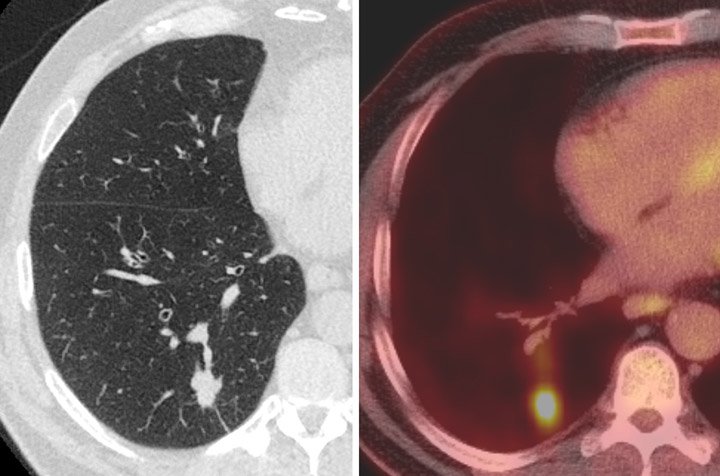

CT (left) and PET-CT (right) image of a small peripheral and clinically asymptomatic

lung cancer detected on a baseline lung cancer screening examination. The cancer

was resected via minimally-invasive surgery and the patient is now

free of cancer and doing well.